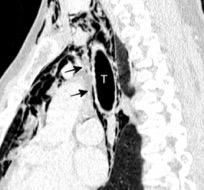

Líneas paraespinales formando un “paréntesis” por encima del diafragma. El signo señala el origen “intratorácico” de la lesión.

Conrad A et al. Pott’s disease associated with large and multiple abscesses in a 30-year-old migrant from Chad. BMJ Case Rep 2018

(lesiones toracoabdominales) La divergencia de las líneas paraespinales apunta a lesión toracoabdominal, que desde el tórax desciende y penetra en el abdomen.

Signo del “iceberg” positivo en Tb vertebral

Afectación por vía hematógena. Región dorsolumbar más frecuente. Afectación inicial: irregularidad de los platillos vertebrales, disminución del disco intervertebral con esclerosis ósea adyacente. Kim. Radiographics.2001